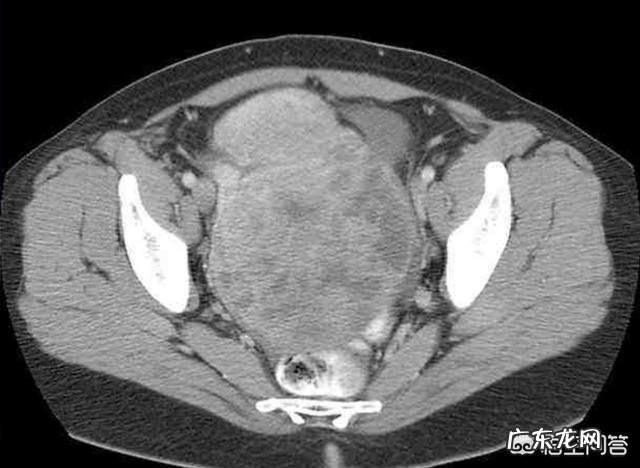

上图是卵巢肿瘤的CT横断面图像 。